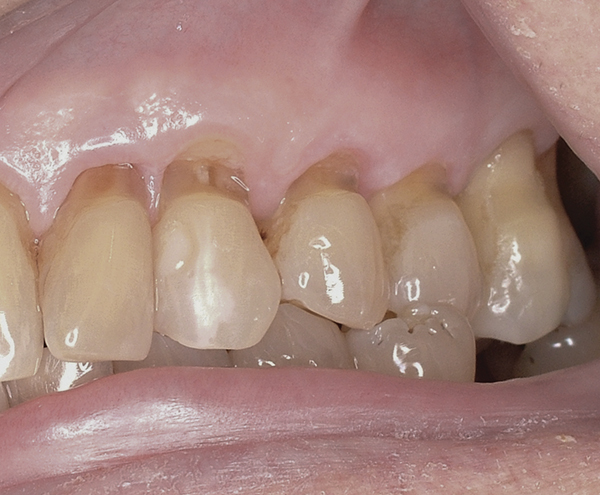

A major predisposing factor to dentin hypersensitivity is exposed root surfaces (Figure 2 through Figure 4).33 Contributors to dentin hypersensitivity include enamel loss with exposed dentin due to attrition and tooth wear caused by bruxism, occlusal habits, and parafunctional activity (Figure 5).34

(Figure 2.) Gingival recession with exposed root surfaces are susceptible to dentinal hypersensitivity non-carious cervical lesions on the facial surfaces of maxillary teeth with symptoms of dentin hypersensitivity and in need of restorations.

Figure 2

(Figure 4.) Gingival recession with exposed root surfaces are susceptible to dentinal hypersensitivity facial surfaces of maxillary teeth with recession with symptoms of dentin hypersensitivity.

Figure 4